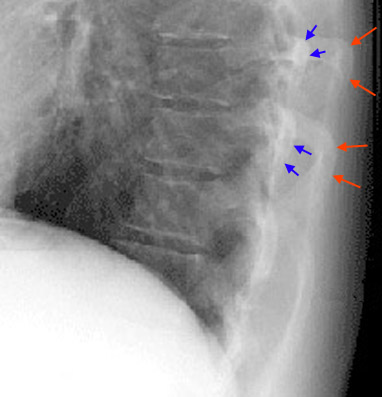

22) The image seen below is a magnified view of a lateral chest x-ray. The blue arrows indicate the left ribs and the red arrows indicate the right ribs. Which of the following statements is true?